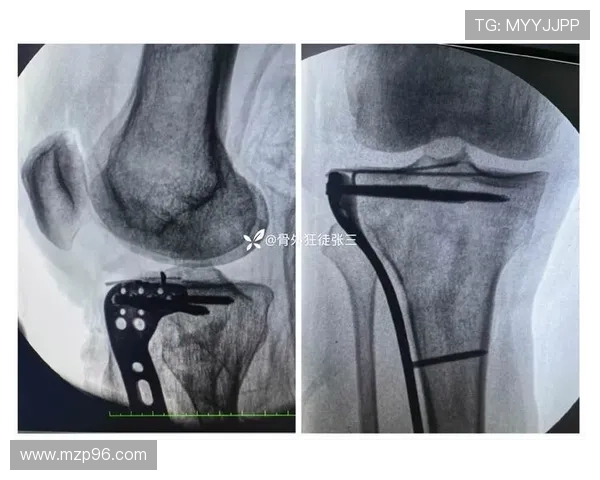

膝微骨折多由反复冲击或过度使用引发,早期症状可能仅为隐痛和肿胀。若忽视治疗,可能演变为慢性损伤,甚至影响职业寿命。因此,选择手术修复,是在科学评估后的理性决定。

此次手术邀请欧洲运动医学领域的知名专家主刀,体现出团队对治疗质量的高度重视。欧洲在足球运动损伤治疗方面经验丰富,拥有成熟的微创技术和康复体系。

名医主刀不仅意味着先进设备和精准操作,更代表一整套系统化的诊疗流程。从术前评估、手术方案制定到术后监测,都以数据和临床经验为支撑,为武磊的恢复提供坚实保障。